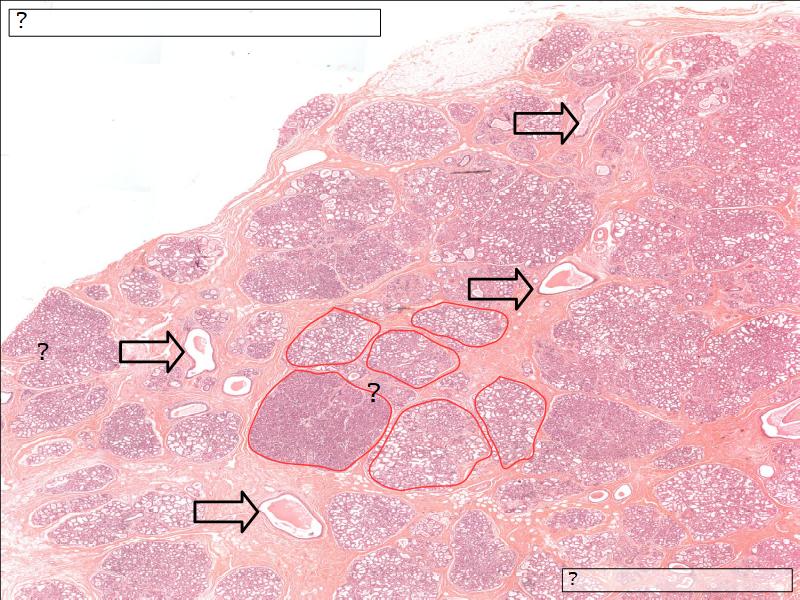

Two stages

- Resting

- Active

Resting and active

Describe the resting mammary gland and compare with the active gland.

(8)

Resting gland

- Connective tissue dominate

- More adipose tissue

- Glandular tissue reduced

Active gland

- Terminal ducts expand

- Forms alveoli

- Connective tissue reduced

- Adipose tissue reduced

- Glandular tissue dominate